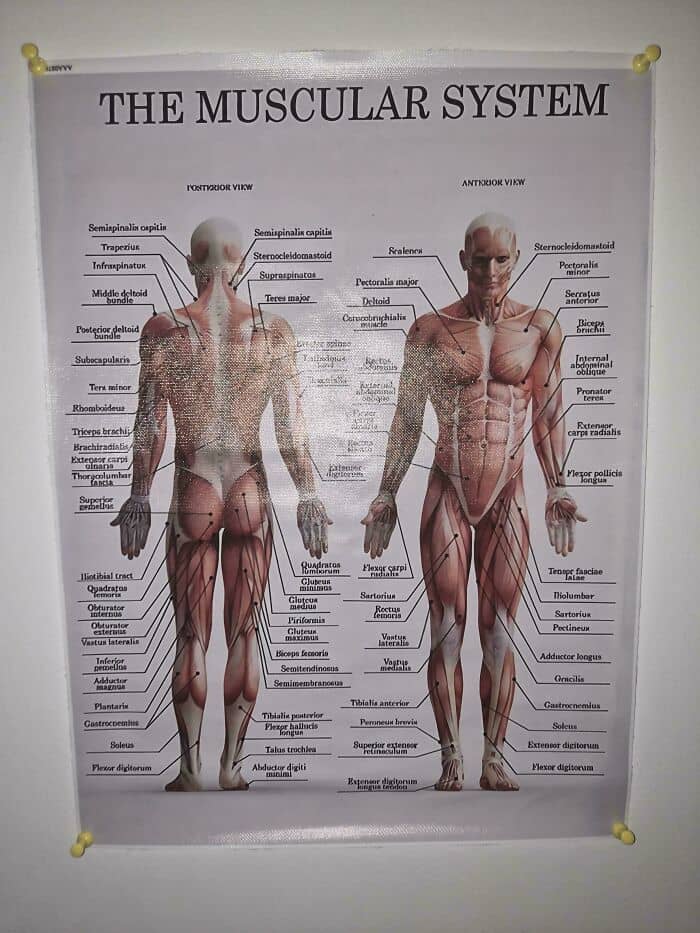

Your nerves are as thin as strings. First time I opened up a body and studied all the anatomy, it was shocking how nerves and blood vessels were incredibly thin. Like we get hit by balls or fall on rocks or do martial arts and dont think much of it but the wiring of your entire body is so thin it’s sobering to realize how fragile we really are.

The spinal cord itself looks and feels like crab meat when it’s pulled out of the vertebrae.

How brittle some bones are. Especially around the neck area.